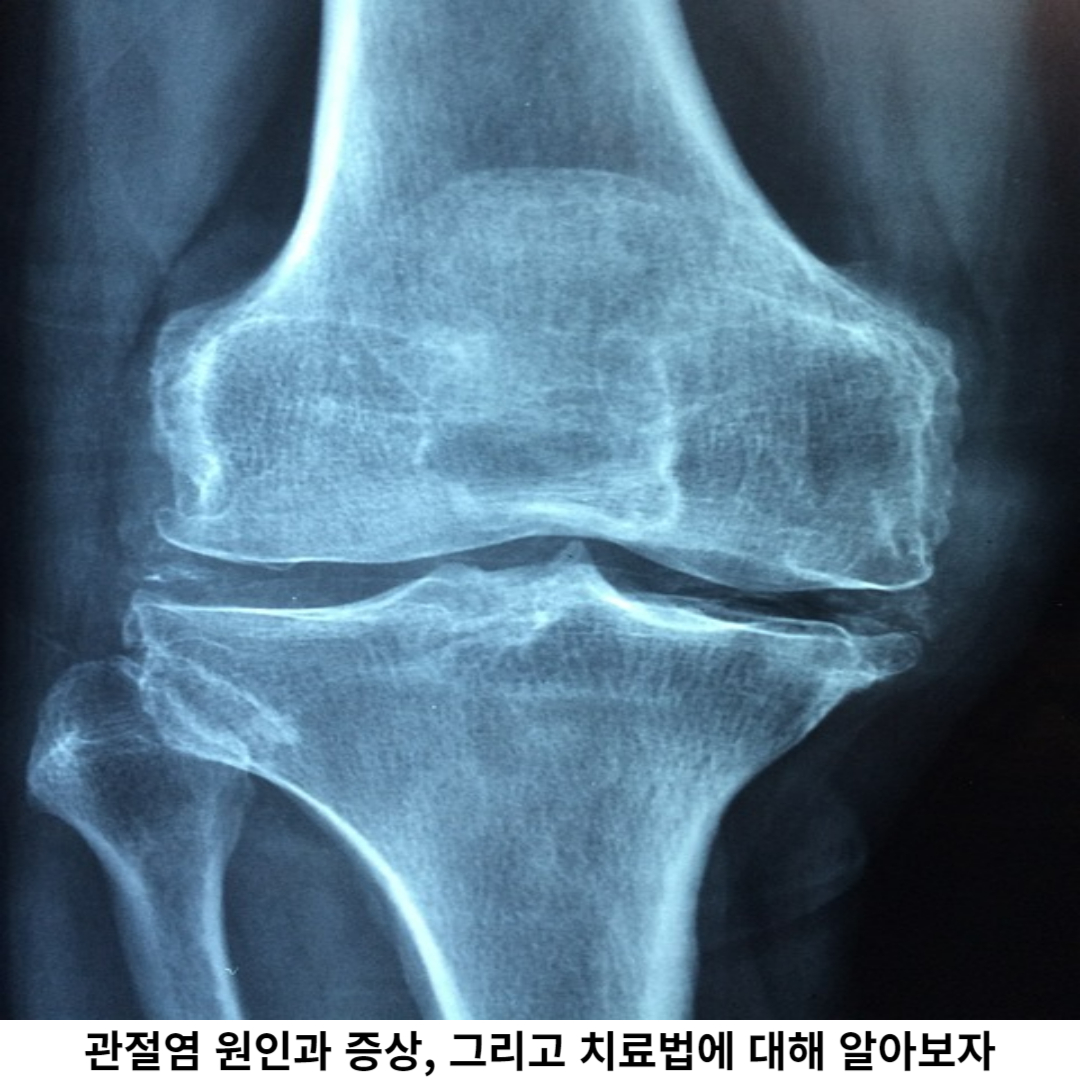

관절염의 증상은 직업과 환경에 따라 다양하지만, 주요 증상으로는 통증, 관절 부종, 관절에 장애가 있습니다. 초기 단계에서는 통증이 약하고 간헐적일 수 있으며, 특히 움직일 때 통증이 증가하여 더 심해집니다.

점차적으로 통증은 심해지고, 관절 주변의 부종이 계속 발생하여 움직임 불편해집니다. 이로 인해 관절의 움직임이 제한되고, 일상생활에서 활동하는 데 어려움을 초래합니다. 또한, 관절 주위의 근육과 인대에도 통증이 발생할 수 있습니다.

관절염은 증상이 진행될수록 증상이 심각해지며, 조기 발견과 적절한 치료가 필요합니다. 통증은 관절염의 가장 흔한 증상이며, 특히 활동 시 더욱 매우 심해집니다.

관절 주변의 염증으로 인해 통증이 발생하며, 특히 무릎, 엉덩이, 손목, 발목, 등의 관절에서 자주 나타납니다. 이러한 통증은 일상생활 활동 범위가 제한되며, 특히 계단 오르내리기, 앉았다 일어날 때, 길을 걷는 등의 동작 시 더욱 불편해집니다.